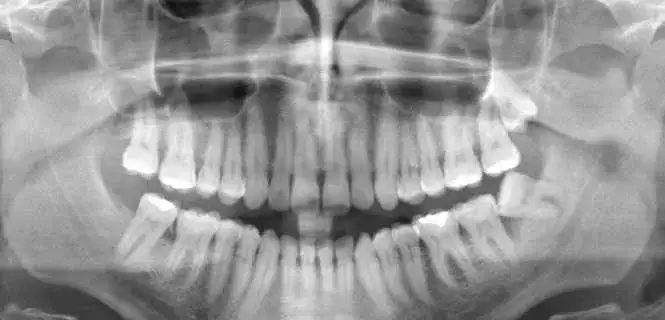

Ile kosztuje zdjęcie panoramiczne zębów? Sprawdź ceny w Polsce

Sprawdź, ile kosztuje zdjęcie panoramiczne zębów w Polsce. Poznaj ceny w różnych miastach i dowiedz się, jakie korzyści niesie to badanie.